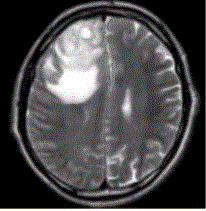

问题 患者女,67岁,头痛伴呕吐1周。既往体健。MR表现如下图。 多形性成胶质细胞瘤的转移途径不包括

选项 A.室管膜 B.淋巴转移 C.脑膜 D.血管周围间隙 E.也可转移至颅外

答案 B